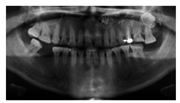

面像曲面体层X线片示37、46缺失,25根充不全,根尖周阴影,26近中邻

面龋深及牙髓,27伸长且根方可见28颊舌向埋伏阻生(图2)。许勒位X线片示,双侧髁突骨皮质完整,形态无异常(图3)。